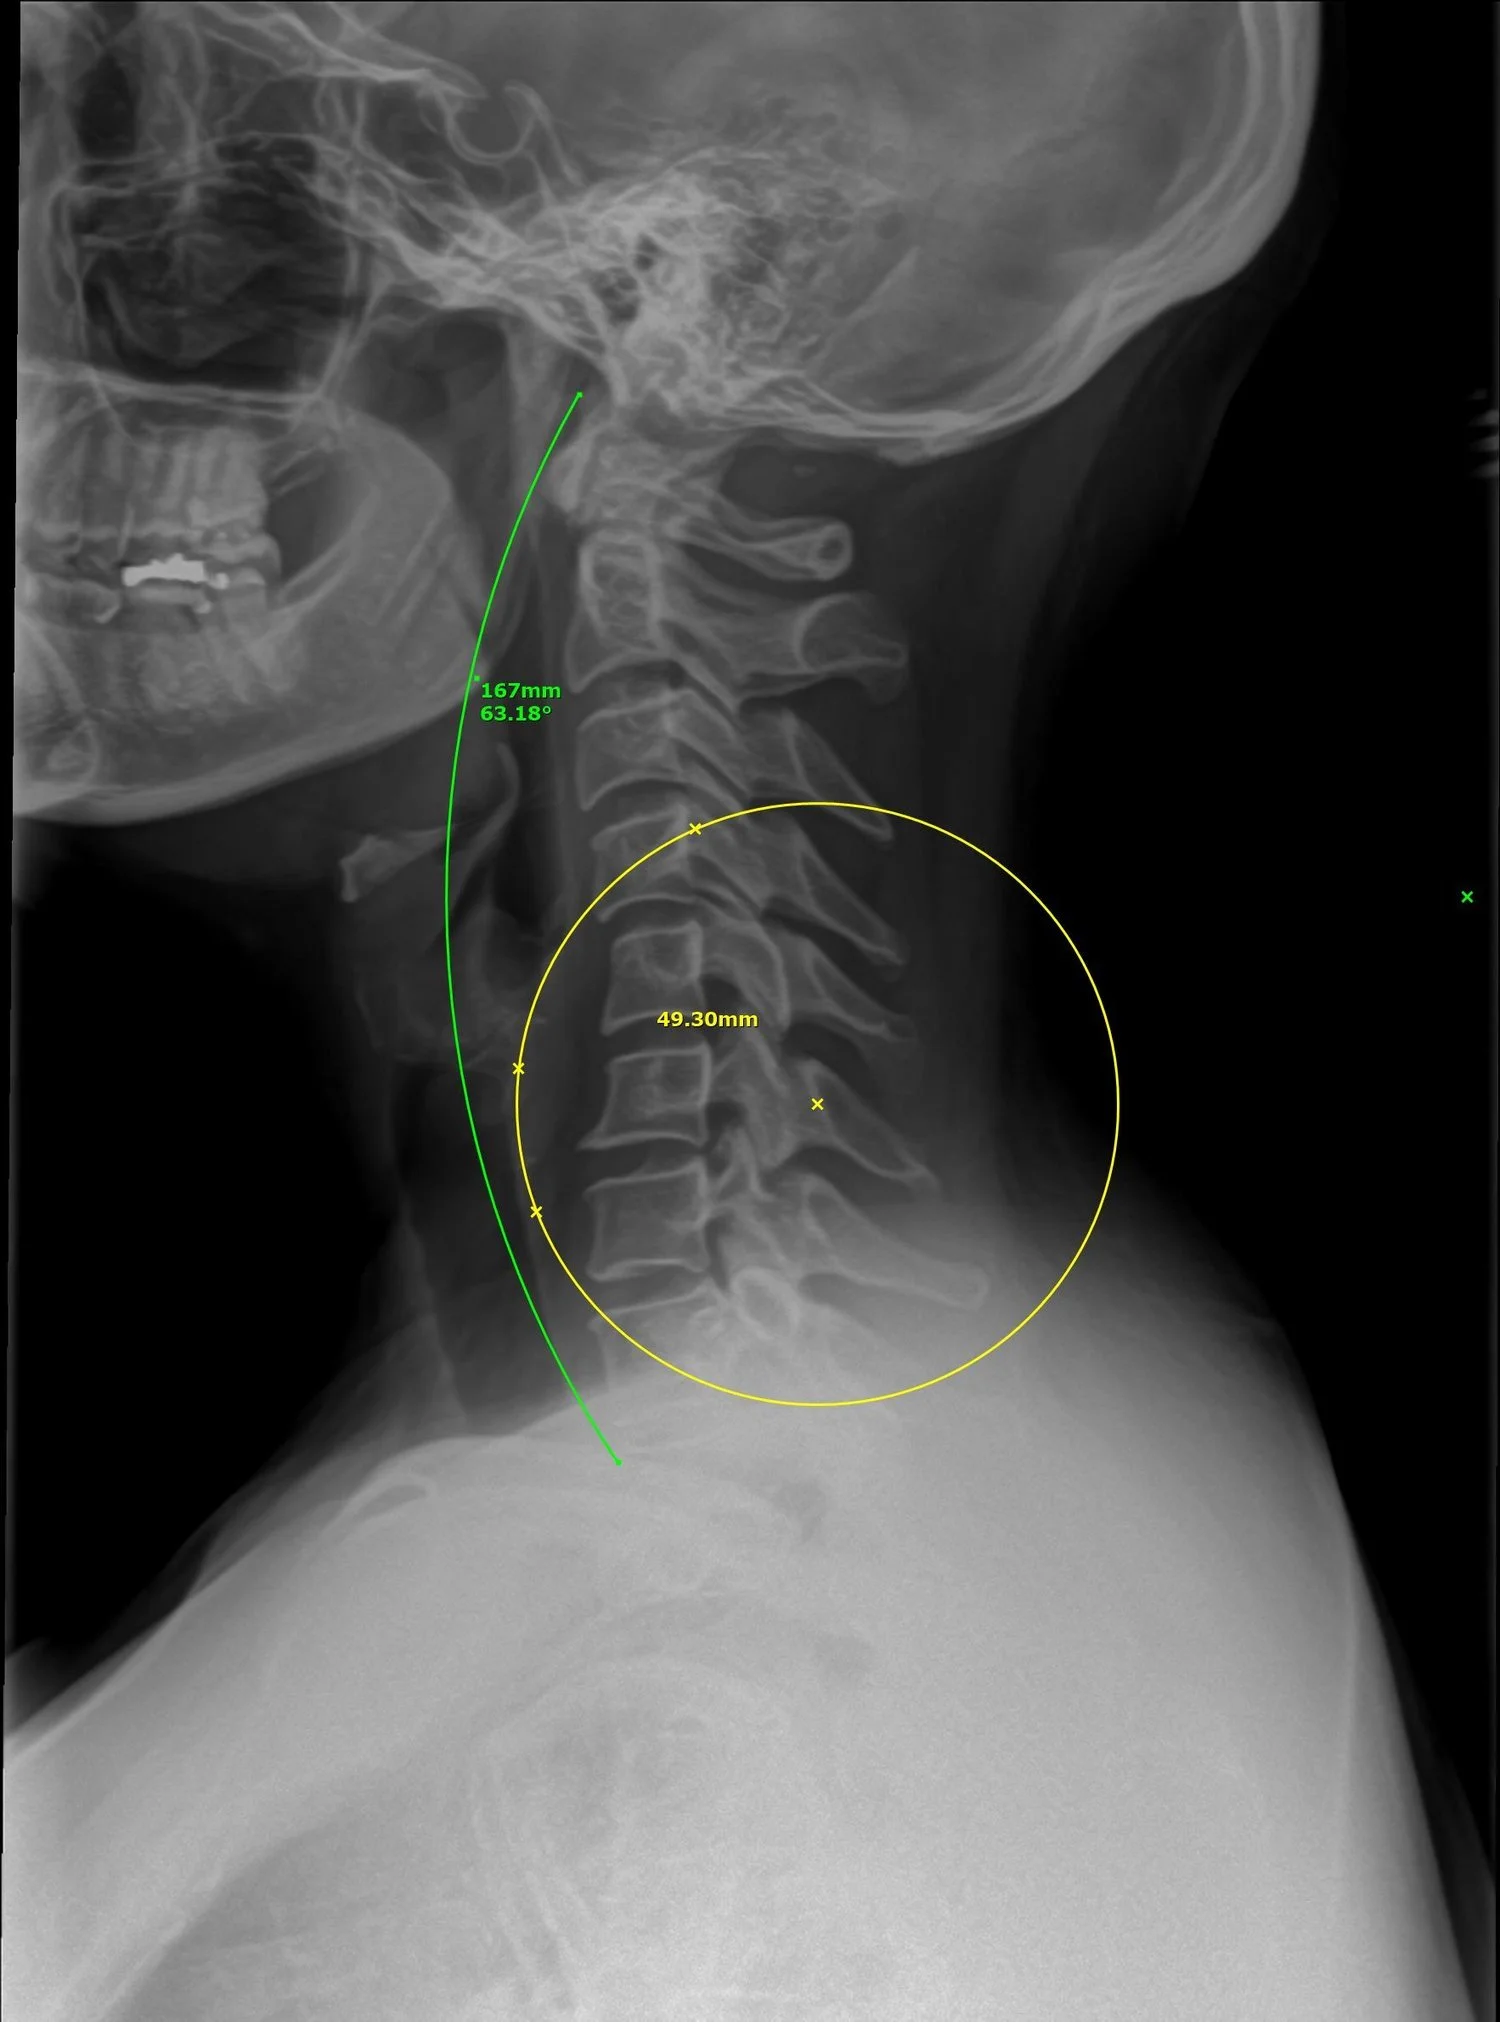

Digital plain spinal X-rays are diagnostic imaging tests that use a digital X-ray machine to create detailed images of the spine. These images can help doctors identify spinal conditions, such as fractures, arthritis, and spinal deformities.